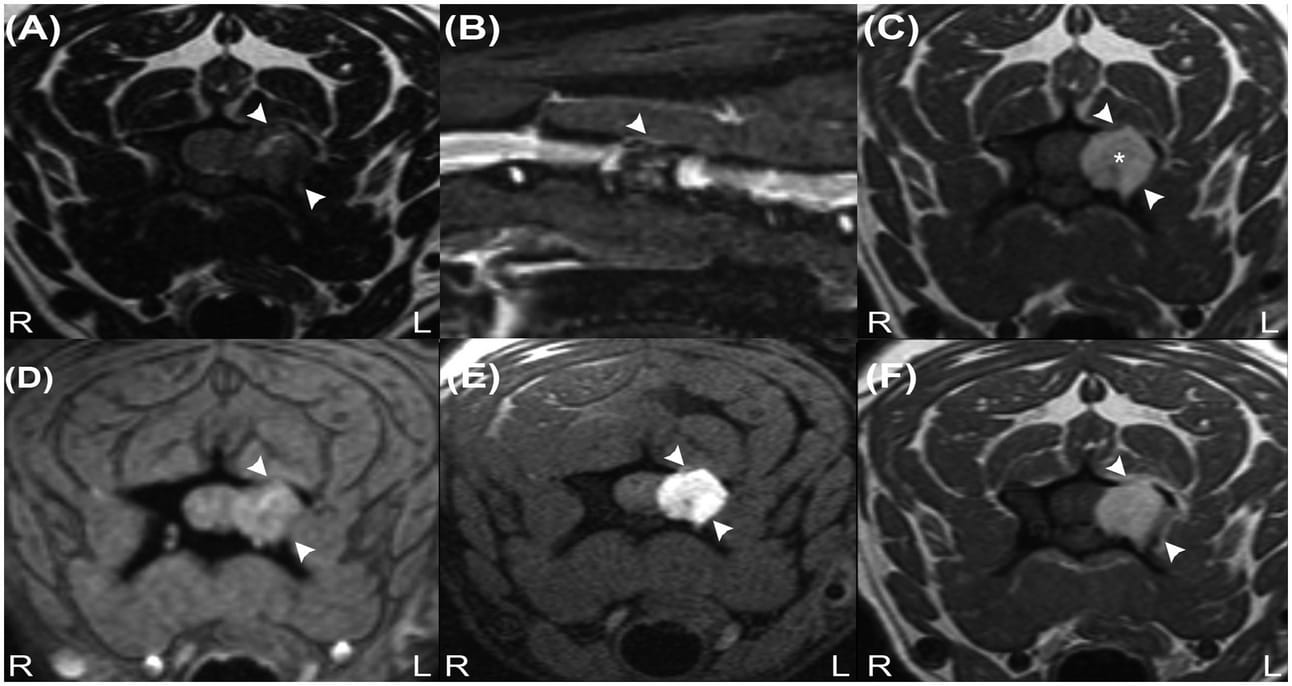

ransverse T2W image (A), sagittal STIR image (B), transverse precontrast T1W images (C), transverse T2* image (D), transverse T1W fat-suppressed precontrast image (E) and transverse contrast-enhanced T1W image (F) revealing an extradural mass at the level of the C4 vertebra (arrowheads). Note the characteristic hyperintense signal on image (C) (asterisk) and signal suppression on image (B) but absence of signal suppression on image (E), indicating that the lesion does not contain fat tissue. The absence of signal voids on image (D) reveals that haemorrhage and calcifications are unlikely to be present in the mass.

The diagnostic approach included MRI and CT imaging to characterize the lesion's properties and guide treatment planning. MRI used a 1.5-Tesla system, revealing a hyperintense T1-weighted and isointense T2-weighted extradural mass at the left lamina of the C4 vertebra. The CT scans were performed using an 80-slice helical scanner, further detailing the lesion's location and involvement with surrounding structures. Treatment involved surgical debulking followed by radiotherapy and melanoma vaccine administration.

The mass demonstrated T1-weighted hyperintensity and T2-weighted isointensity, common in melanocytic lesions due to melanin’s paramagnetic properties. Histopathological examination confirmed the diagnosis of a malignant melanocytic tumor. Despite initial successful management, the dog eventually exhibited recurrence of symptoms 18 months later, leading to euthanasia. Notably, this case represents a rare instance of a melanocytic tumor at this location, with detailed documentation of the MRI and CT imaging characteristics.